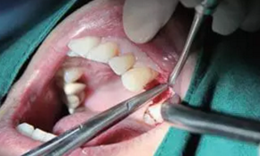

從圖1可以看出患者缺牙區(qū)的間隙充足,牙齦健康,頰側(cè)軟組織略有凹陷。

圖1 缺牙區(qū)的頰側(cè)和口內(nèi)照片